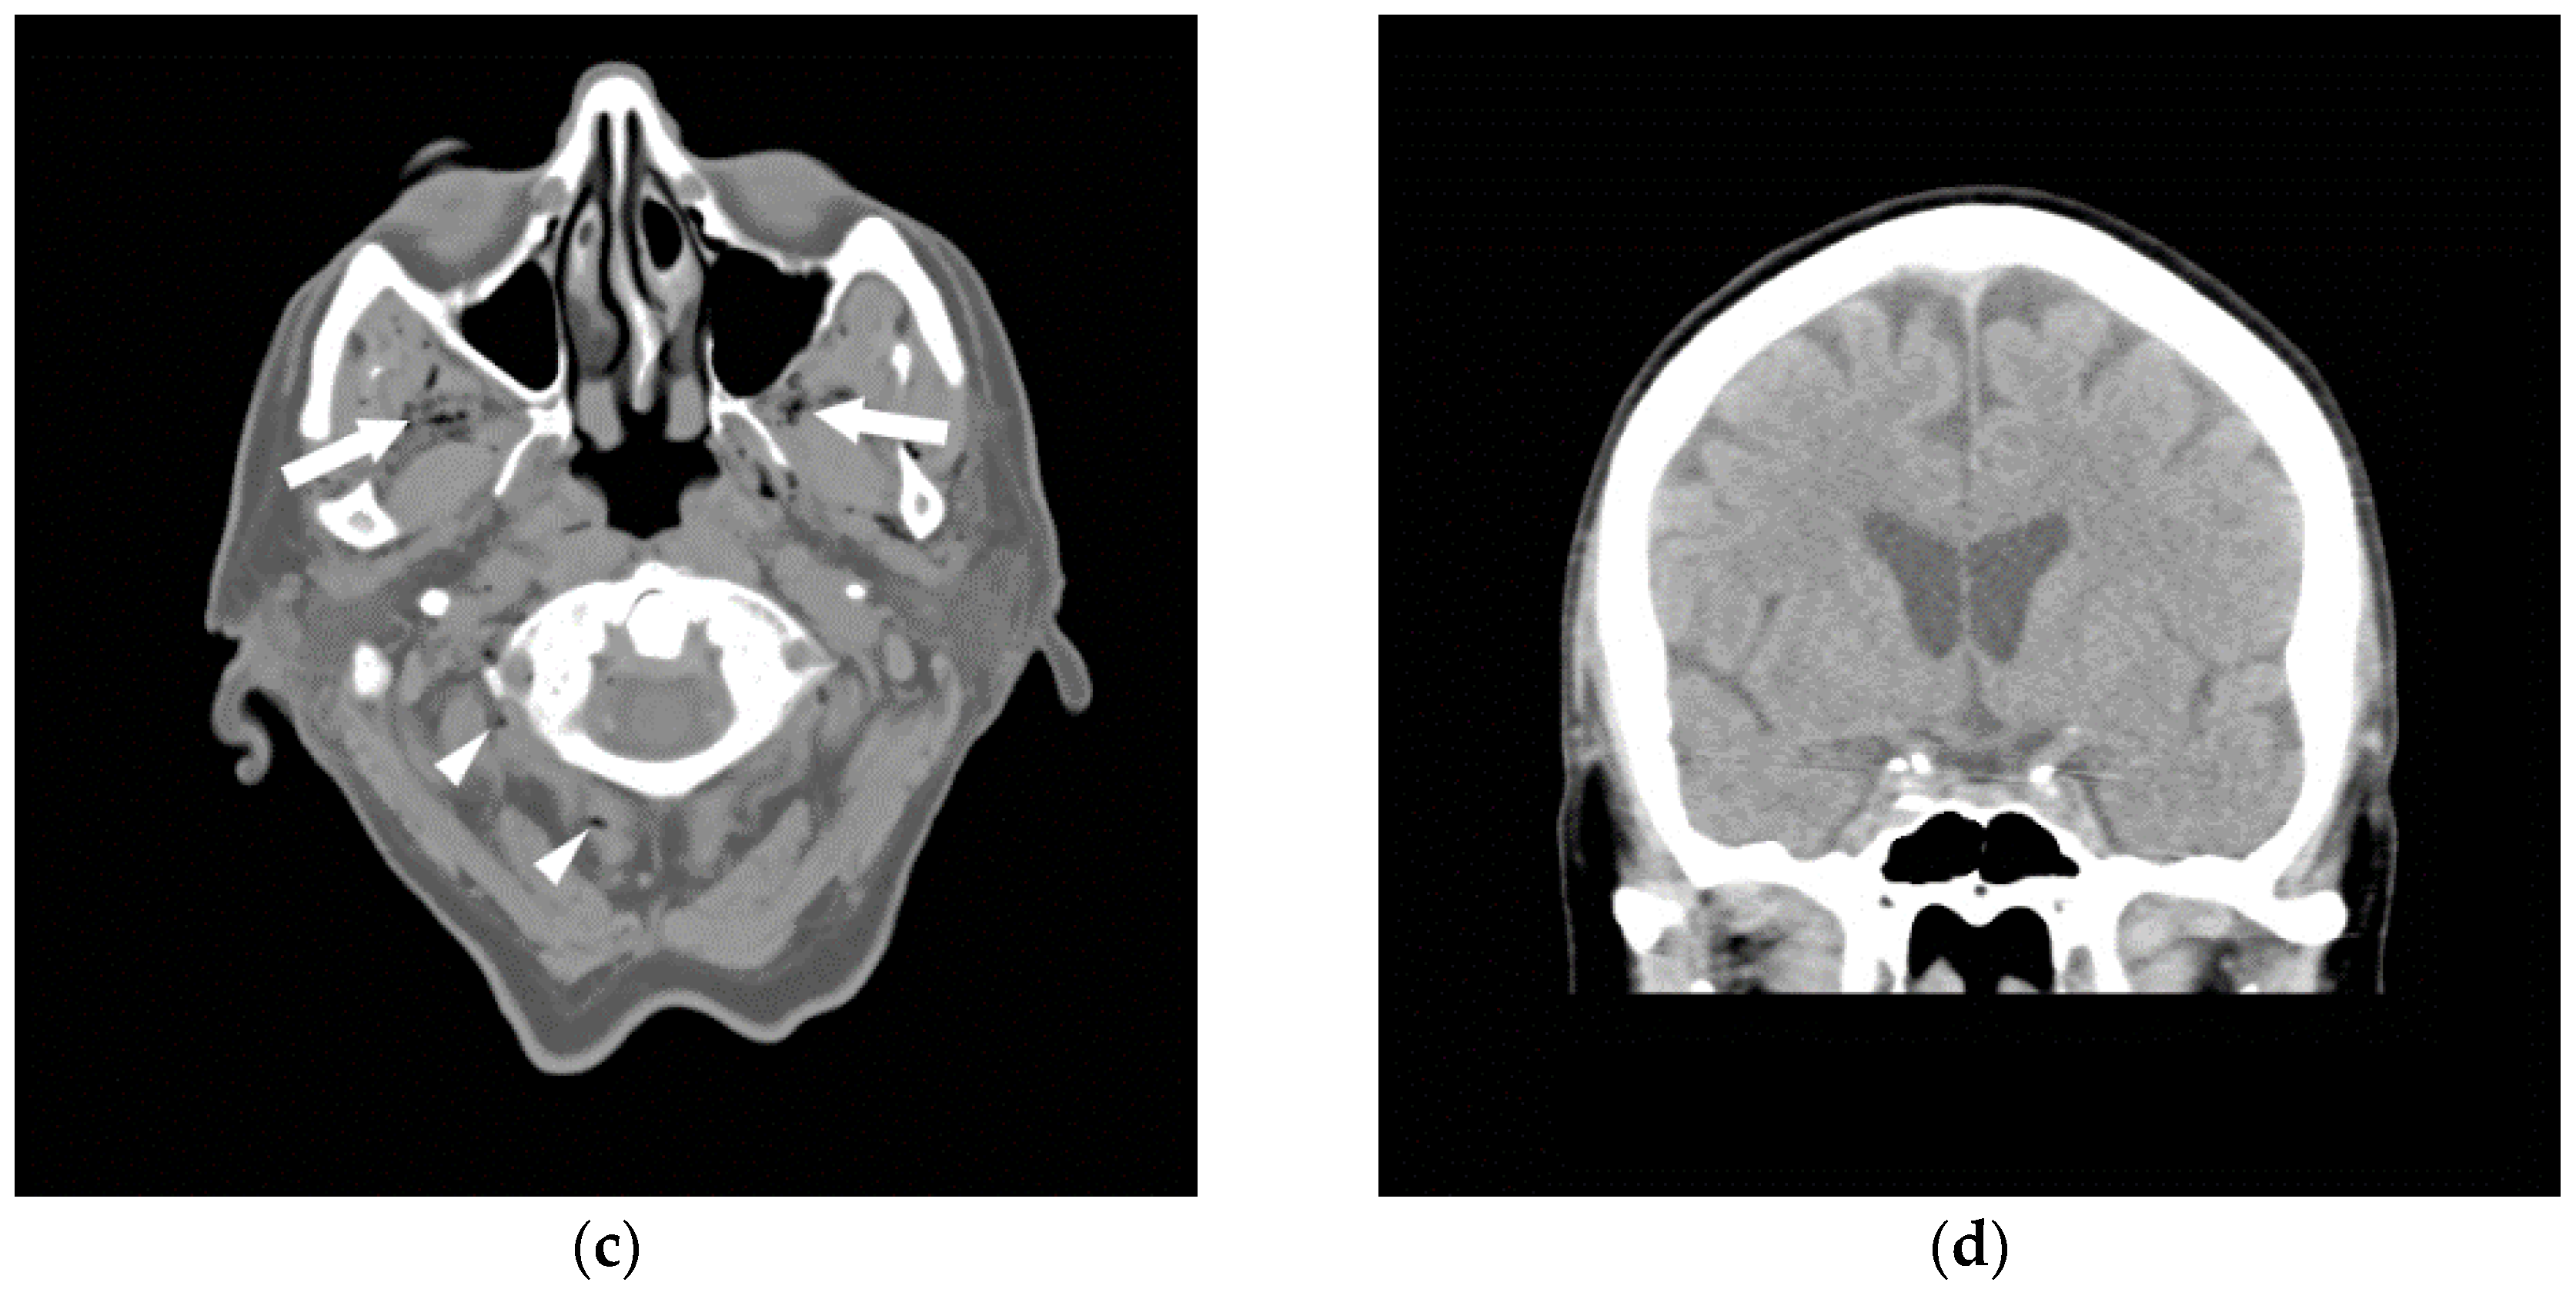

Figure 2.

A 61-year-old male underwent an initial femoral angiogram (a), which revealed a small amount of air in the tubing of the side port (arrowhead) that had traveled into the superficial femoral artery (arrows). As the lower extremity arteriogram (b) revealed no visible distal emboli, it was presumed the air was resorbed. There were no adverse sequelae.